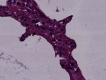

Difficulties have risen while managing Acute Respiratory Distress Syndrome (ARDS) caused by COVID-19, although it meets the Berlin definition. Severe hypoxemia with near-normal compliance was noted along with coagulopathy. Understanding the precise pathophysiology of this atypical ARDS will assist researchers and physicians in improving their therapeutic approach. Previous work is limited to postmortem studies, while our report addresses patients under protective lung mechanical ventilation. An open-lung minithoracotomy was performed in 3 patients who developed ARDS related to COVID-19 and were admitted to the intensive care unit to carry out a pathological and microbiological analysis on lung tissue biopsy. Diffused alveolar damage with hyaline membranes was found, as well as plurifocal fibrin microthrombi and vascular congestion in all patients' specimens. Microbiological cultures were negative, whereas qualitative Reversed Transcriptase Polymerase Chain Reaction (RT-PCR) detected SARS-CoV-2 in the pulmonary parenchyma and pleural fluid in two patients. COVID-19 causes progressive ARDS with onset of severe hypoxemia, underlying a dual mechanism: shunt effect through diffused alveolar damage and dead space effect through thrombotic injuries in microvascular beds. It seems reasonable to manage this ventilation-perfusion ratio mismatch using a high dose of anticoagulant combined with glucocorticoids.